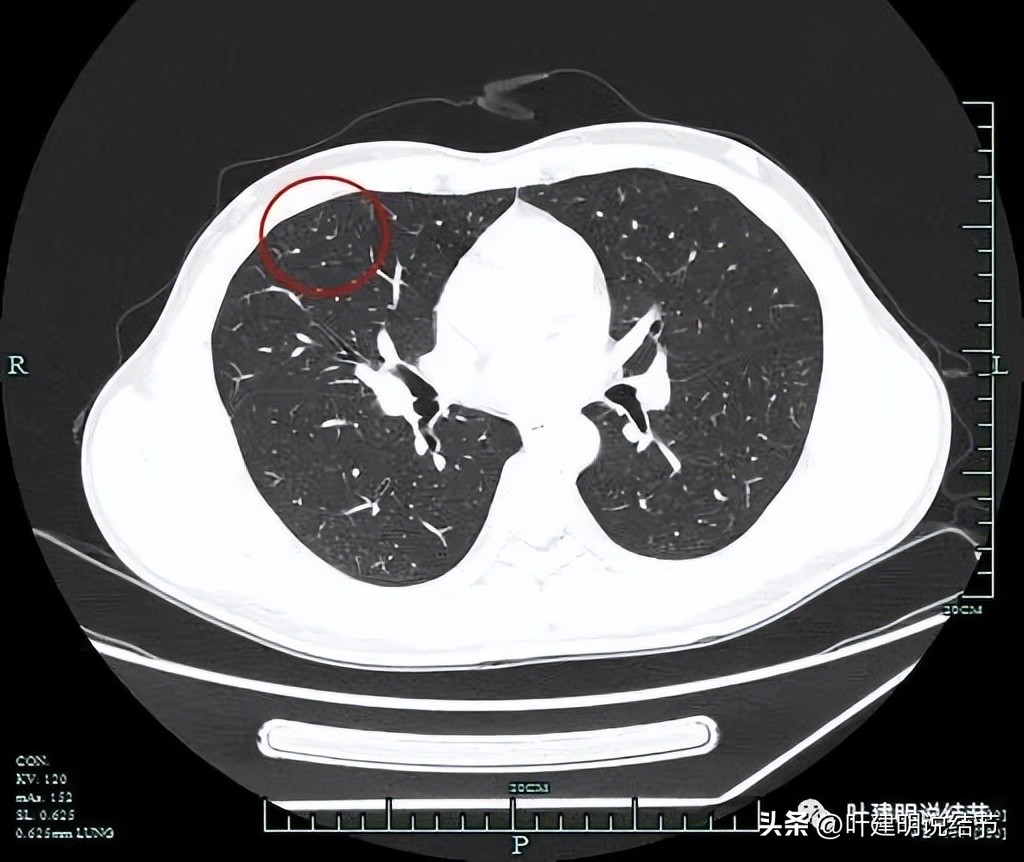

再来看靶扫描影像:

右肺中叶多发结节,主病灶与次病灶均为磨玻璃密度,主病灶瘤肺边界清,轮廓也很清,并有血管进入,总体实性成分不明显,但因明显的血管征,考虑应该至少微浸润性腺癌可能性大,也不能完全除外浸润性腺癌的贴壁型,可以考虑手术治疗;次病灶位于近肺门部,也是磨玻璃结节,而且边不光整,密度也显各不均匀,怀疑原位癌或微浸润性腺癌可能性大。虽然目前小而没有实性成分,但如果主病灶要干预,此灶也得一并切除;病灶三由于非常微小,而且密度甚高,虽有空泡征,仍考虑是良性的可能性大得多(空泡征或空腔征在实性结节中不适用作为恶性特征表现之一)。